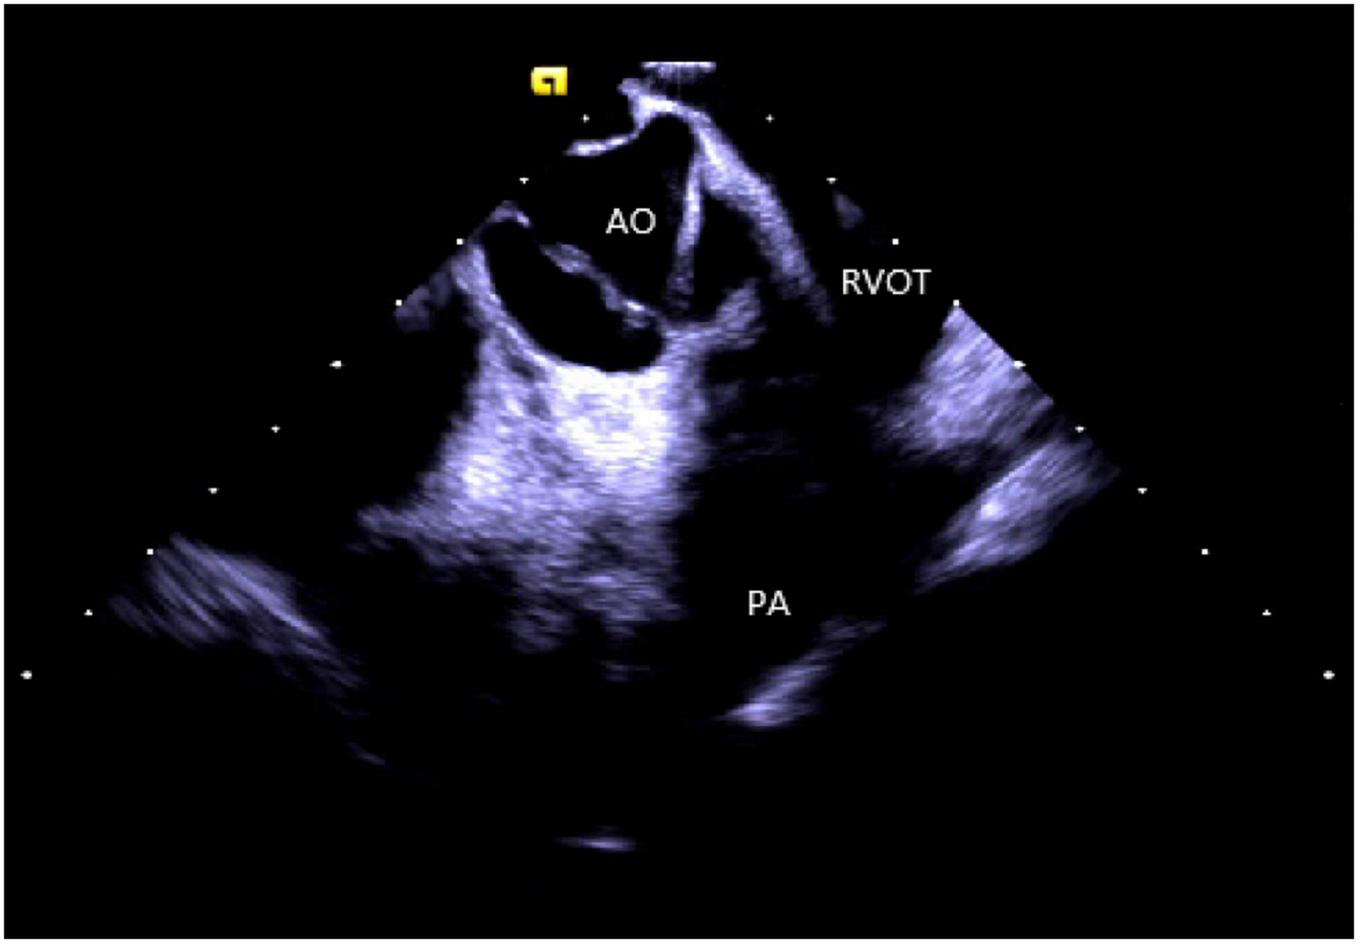

Right ventricular modeling: Based on the HomeView position, the ultrasound sector rotated clockwise toward the RA posterior wall, bending the P curve and directing the catheter into the RV along with the TV orifice. With additional clockwise rotation, the RVOT came into view, along with the long axis of the pulmonary artery, the short axis of the aorta, and the aortic sinus (Figure 3). The catheter was then rotated counterclockwise toward the RV free wall and made an L-bend, thereby showing the RV, LV, moderator band, interventricular septum, and LV anterolateral papillary muscle. Additional downward movement of the catheter to the lowest apical position resulted in the loosening of the L and P bends. Then the catheter was rotated counterclockwise toward the bottom of the RV displaying the moderator band and the papillary muscle of the posterior RV. A continuous counterclockwise rotation toward the RV free wall showed the RV anterior papillary muscle, the free wall of the tricuspid annulus, the subvalvular reflex, and a part of RA (Figure 4). At this point, the RV modeling was complete.

FIGURE 3

The short axis of the aorta. AO, aortic valve; RVOT, right ventricular outflow tract; PA, pulmonary artery.